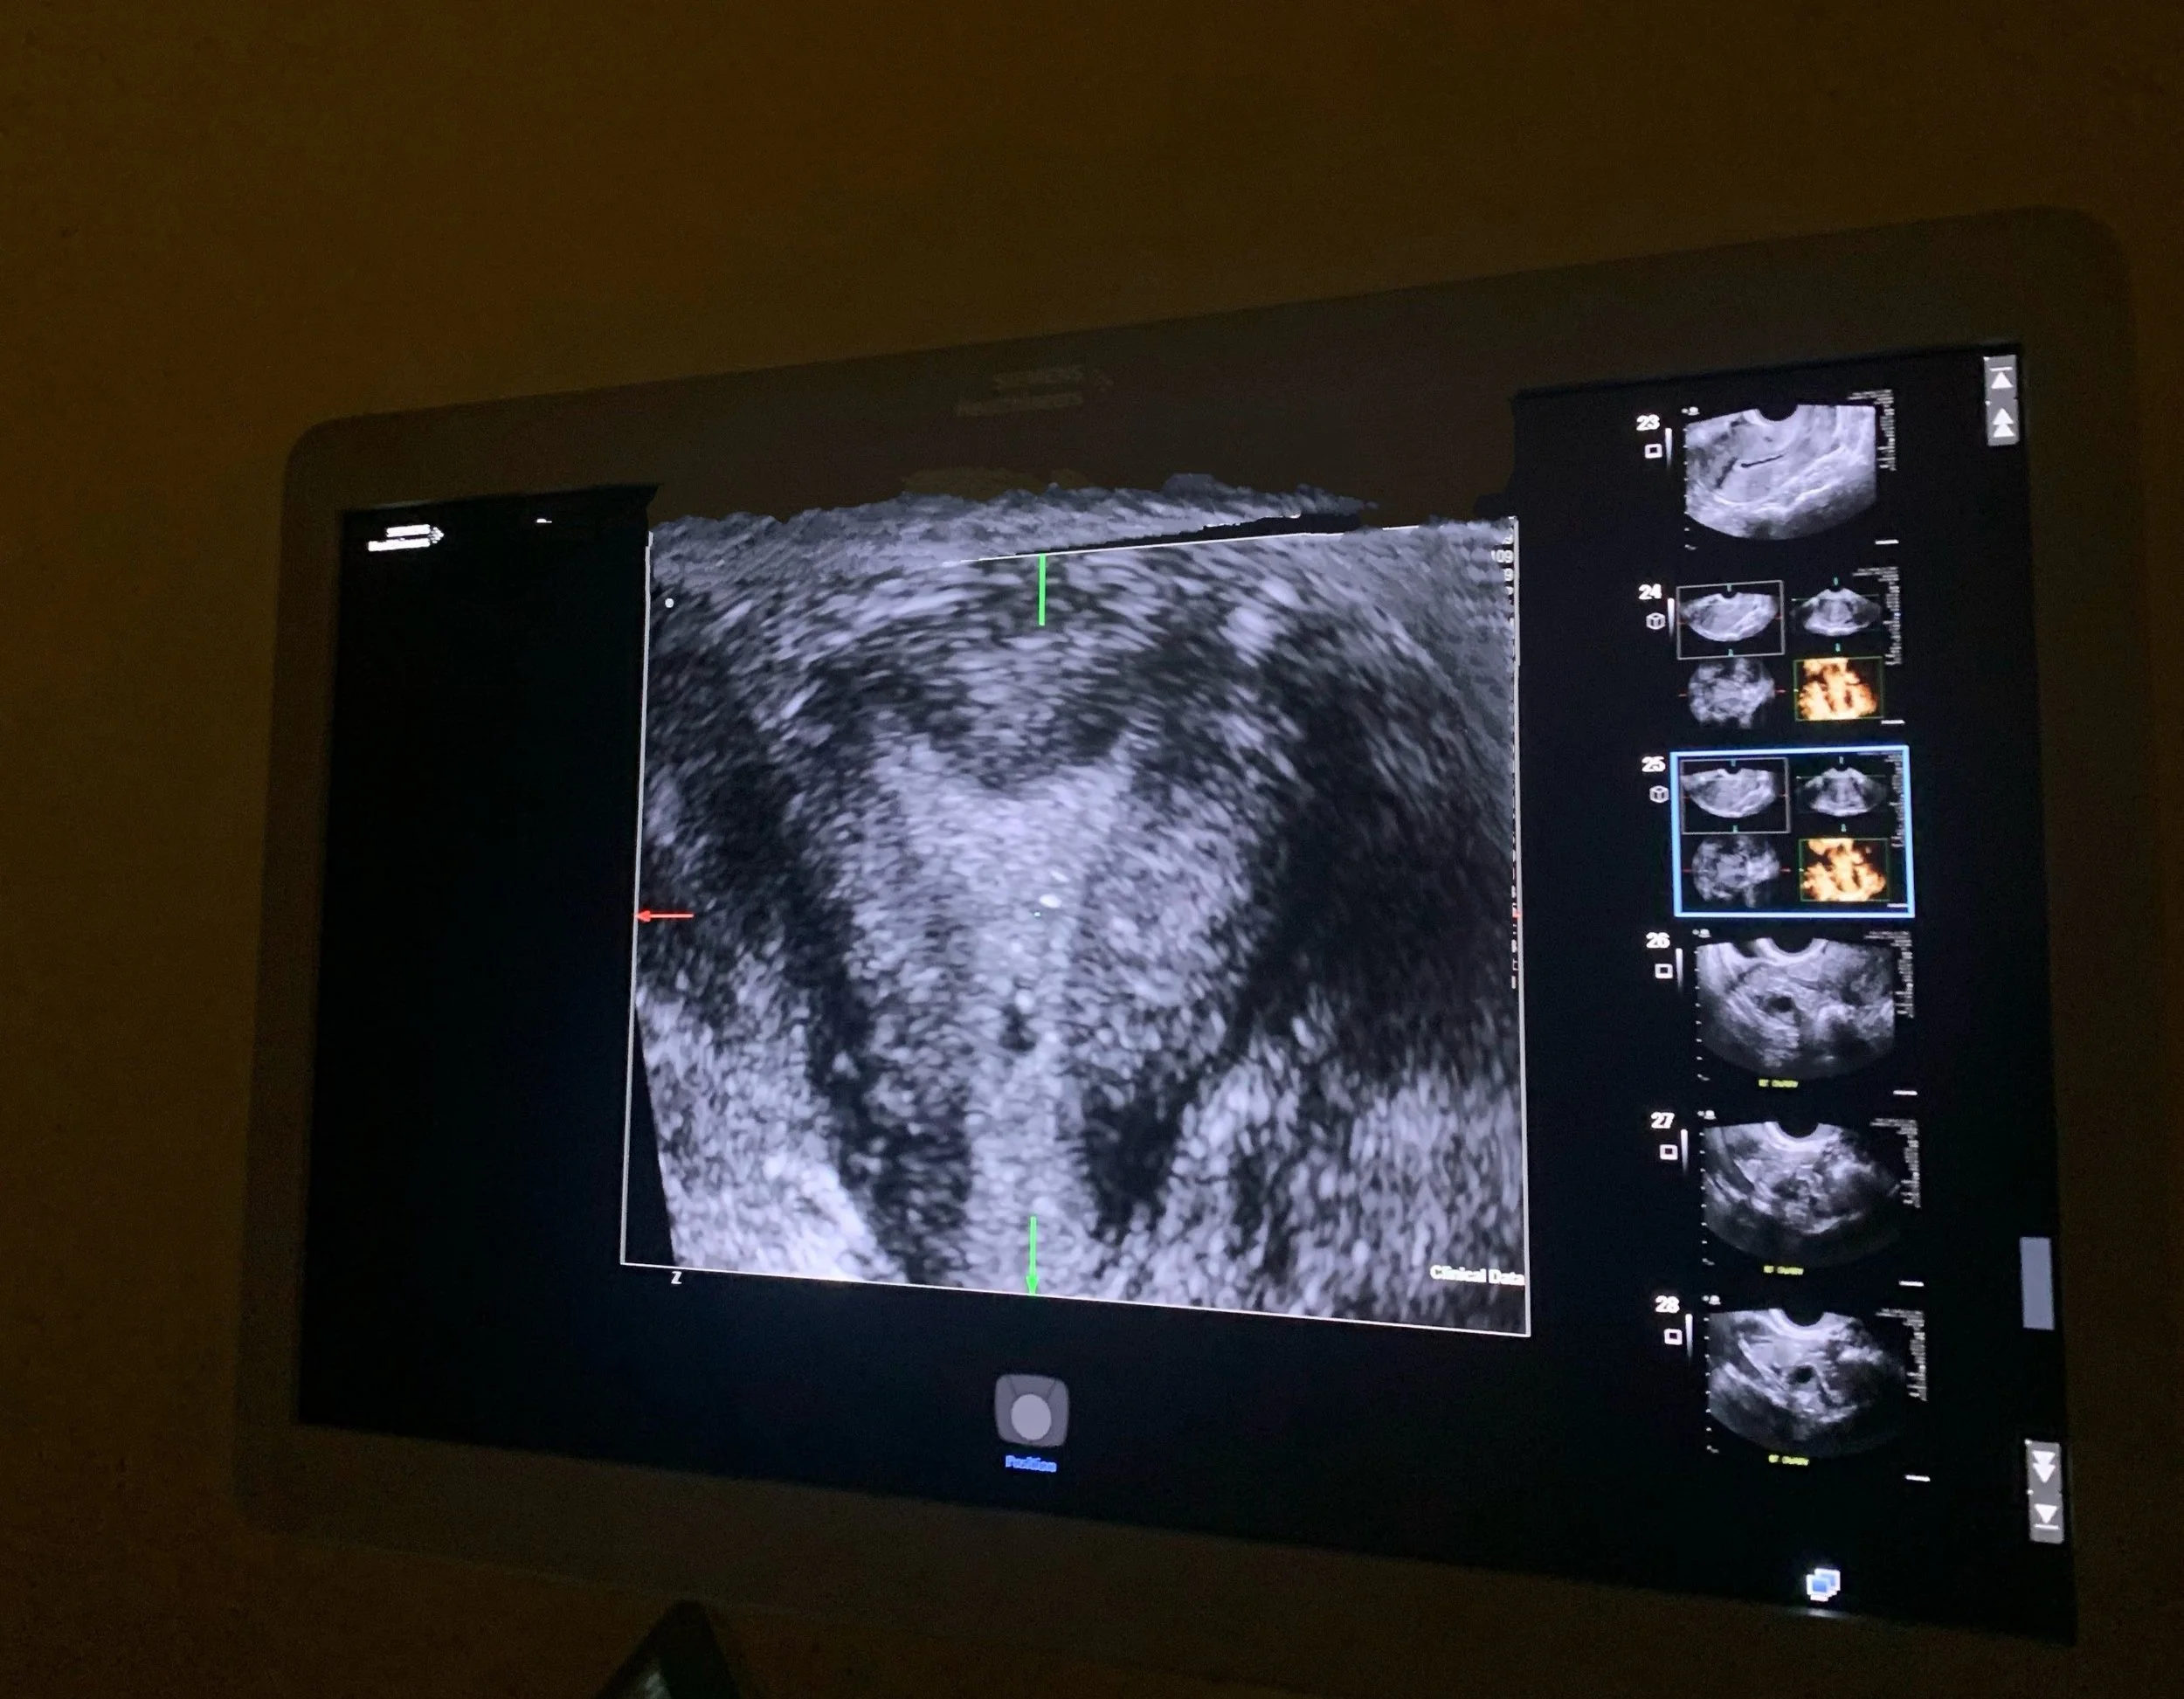

The HSG results indicated that I might have a misshapen uterus—potentially bicornuate—which could make it harder to conceive and carry a pregnancy to term. To investigate further, they ordered a saline sonogram.

Good news—it's not bicornuate! My uterus is only slightly misshapen (classified as arcuate). This will have no impact on my ability to get pregnant or carry a pregnancy to term. Whew, and YAY!